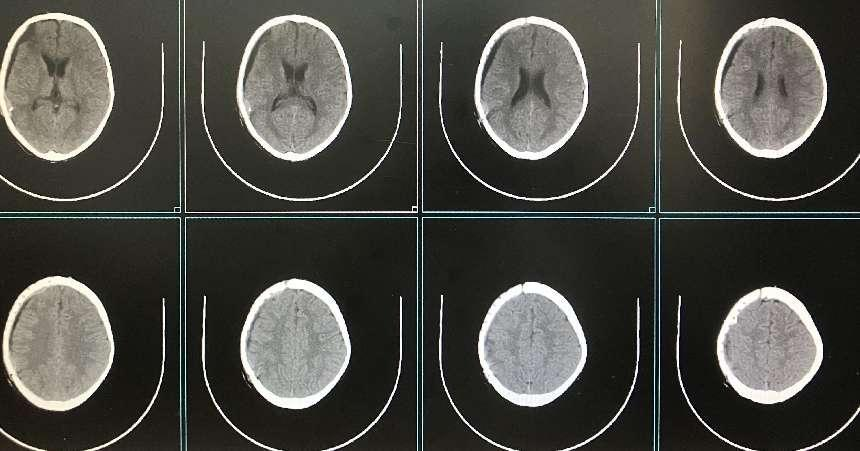

术后CT

经过充分术前检查、讨论,并制定周密的手术方案。由池超超副主任医师主刀,周元鼓副主任医师配合进行手术,术中池超超副主任医师取三维塑形PEEK板置于骨窗,精准嵌合满意后,以颅骨锁、PEEK片、钛钉固定良好,手术顺利完成。

该手术为柳州市首次应用新型材料进行儿童颅骨修补,手术的成功开展,标志着广西科技大学第一附属医院神经外科在儿童颅骨修补领域再上一层楼,达到区内前列水平。